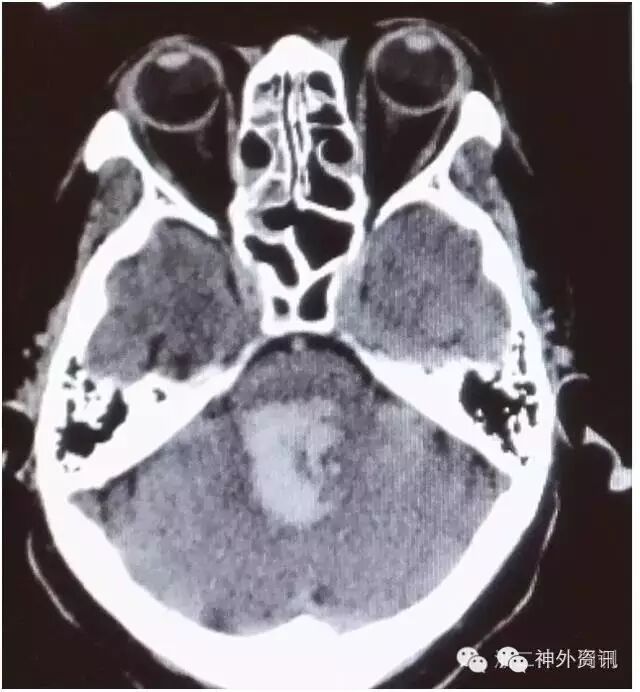

辅助检查: CT:小脑、脑干后部血肿,破入第四脑室及两侧侧脑室后角。按多田氏公式计算血肿量(体积=π/6×长×宽×层面数×层厚)约为20ml(图1)。

图1. 入院CT检查示桥脑出血,血肿约20ml。